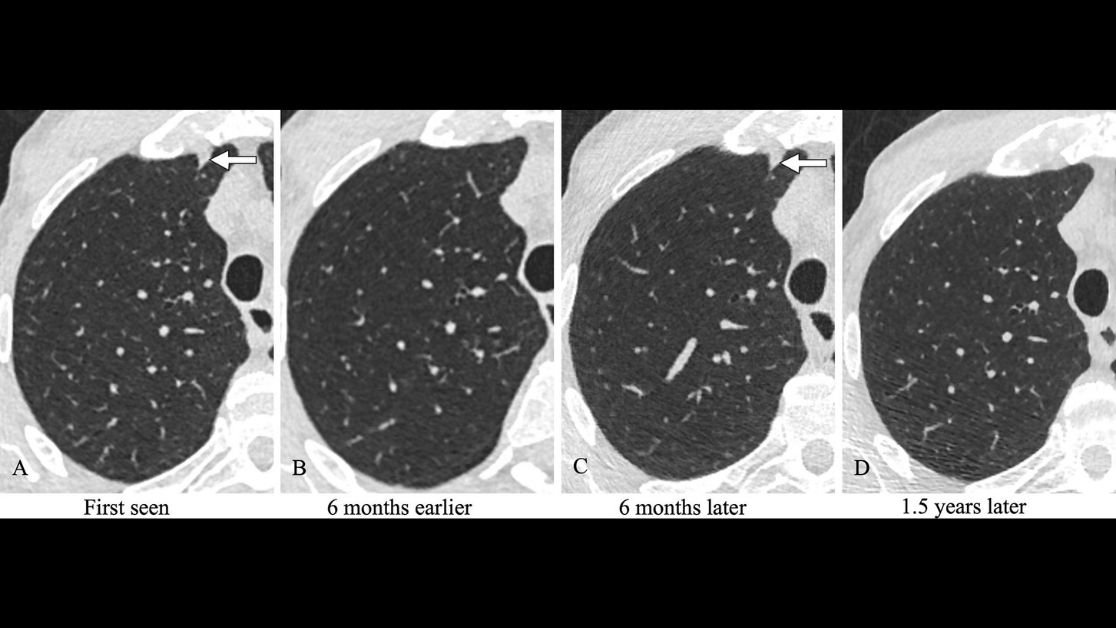

Newly detected solid costal pleura–attached noncalcified nodules at annual screening LDCT may not require immediate follow-up. bit.ly/2XpDE2R #LungScreening #I-ELCAP